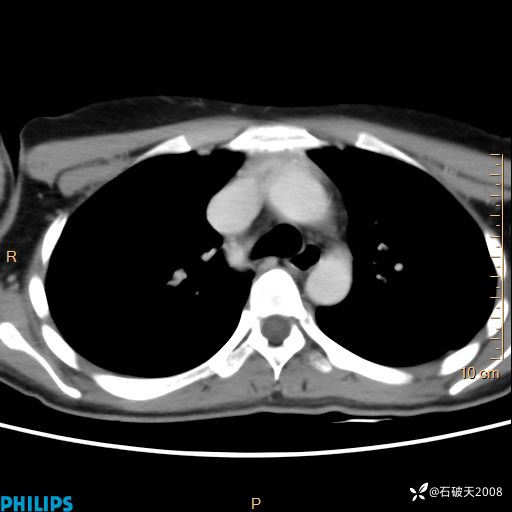

影像诊断要密切结合临床,真的很有必要(病理已公布)

女 21岁 主 诉:发现右侧颈部肿物18年余。

现病史:18年余前患者无明显诱因发现颈部偏右侧有一肿物,具体大小不明确,咳嗽、憋气时肿物增大,局部无疼痛,无吞咽不适,无胸闷及呼吸困难,至当地医院检查考虑良性病变(具体不详)并未做特殊处理,现患者自觉肿物随年龄增长而进一步变大,今日至我院行颈部CT平扫+增强提示:1.右侧颈根部、锁骨上窝及纵隔内异常密度影,考虑良性病变,淋巴管瘤?囊肿?请结合临床。2.双侧颈部小淋巴结。建议结合临床及其他相关检查。现为行进一步治疗,门诊以“颈部局部肿物”为诊断收住我科,发病来患者神志清,精神可,饮食睡眠可,大小便正常,体重无下降。

冠状位

静脉期